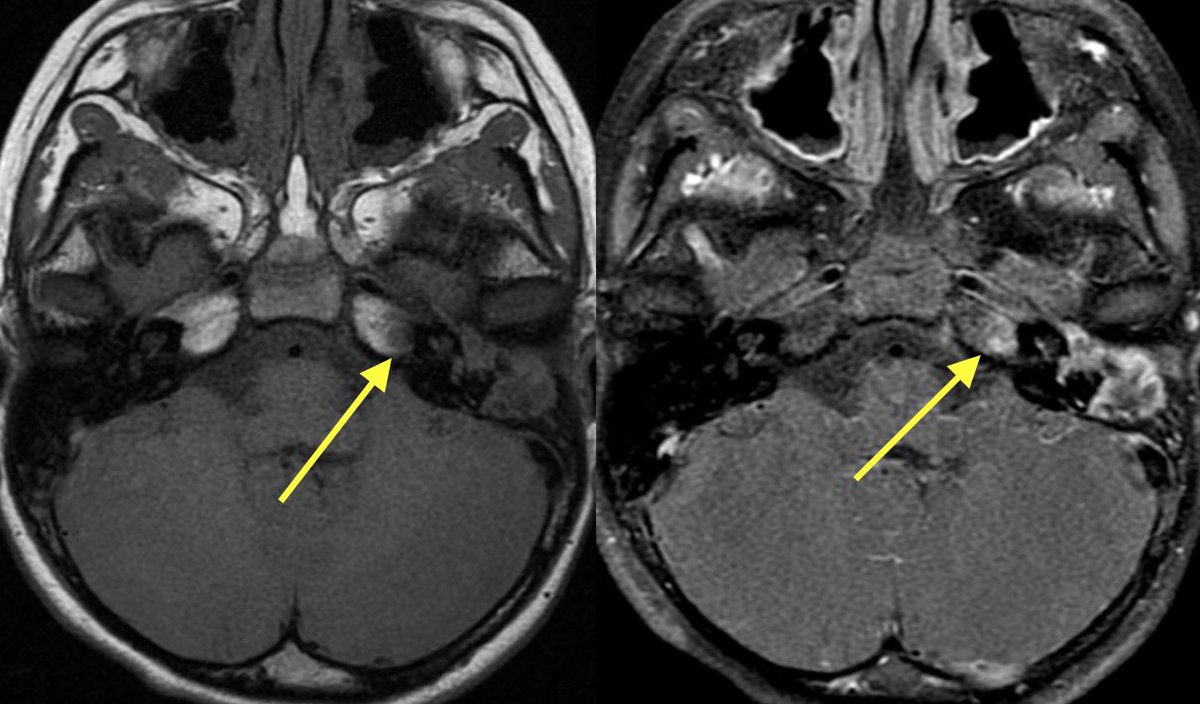

MR shows the extent of the core infarct involving the right BG and MCA-ACA border zone (watershed)

▶️CT-: Subtle loss of GW in the right caudate nucleus